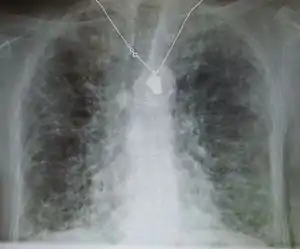

| A chest X-ray demonstrating pulmonary fibrosis believed to be due to amiodarone. | |

Pulmonary fibrosis is suggested by a history of progressive shortness of breath (dyspnea) with exertion. Sometimes fine inspiratory crackles can be heard at the lung bases on auscultation. A chest X-ray may or may not be abnormal, but high-resolution CT will frequently demonstrate abnormalities.[3]